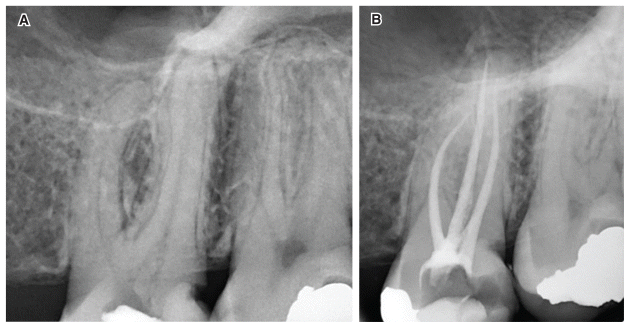

Data were recorded in Excel and analyzed statistically using chi-square tests and multinomial logistic regression. An example of clinical treatments in multi-rooted and single-rooted cases performed in the present study is shown in Figures 1 and 2.